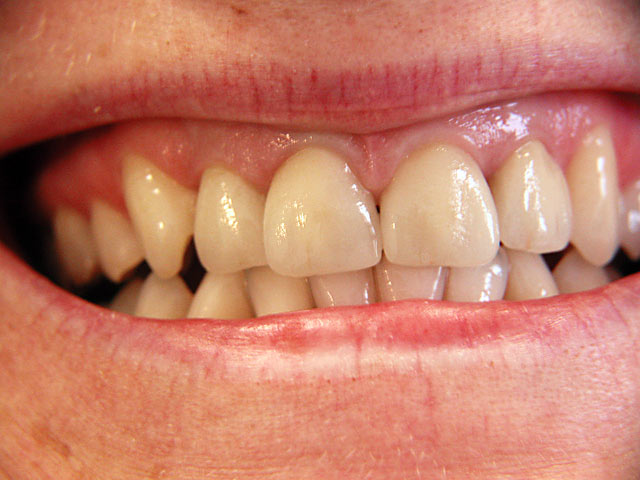

Die folgenden Patientenfälle sollen Ihnen einen Einblick in die Möglichkeiten der modernen Implantation geben.